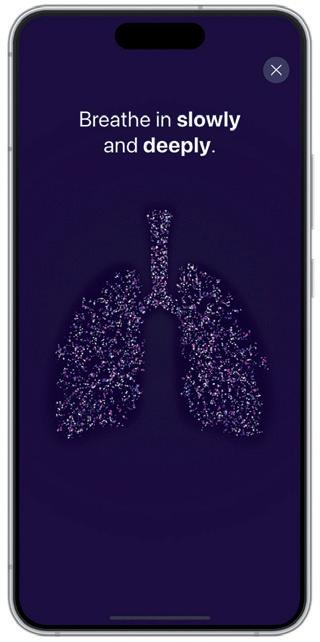

With the development of the new eFlow Integrated nebuliser, PARI has implemented an innovative breath-guiding approach and a novel nebuliser platform that supports and guides the patient to inhale slowly and deeply. Three factors have been successfully combined to optimise the breathing pattern accordingly (Figure 1):

visualisation of inhalation. This can guide the user to inhale slowly and deeply, which, in turn, can increase the I:E ratio and lead to shorter nebulisation times. Such feedback also informs the patient that the inhalation manoeuvre has been performed correctly (Figure 3).

A more detailed inhalation report is given within the app at the end of each therapy to inform patients about their inhalation technique and therefore strengthen their engagement and self-management. This can support patients in their effective inhalation to promote the best possible therapy outcomes. With this new digital feature, PARI sends feedback to guide the patient to an optimal breathing pattern.

The second element to guide patients’ breathing patterns is the user interface on the device. By providing intuitive instructions directly via an illuminated mouthpiece assembly and a vibrating controller, PARI’s new eFlow integrated nebuliser platform effectively trains the patient on the correct breathing pattern during inhalation. A pressure sensor collects real-time data from the inspiratory flow, translating this information into haptic and visual signals that inform the user on whether or not the inhalation is optimal (Figure 2).

Feedback is simultaneously visualised within the new PARI Breath Guide app, which, as an optional feature, is connected to the eFlow Integrated nebuliser via Bluetooth. The visualised breathguiding feature trains a slow, controlled inspiration. The app uses transferred data to provide real-time feedback and a helpful